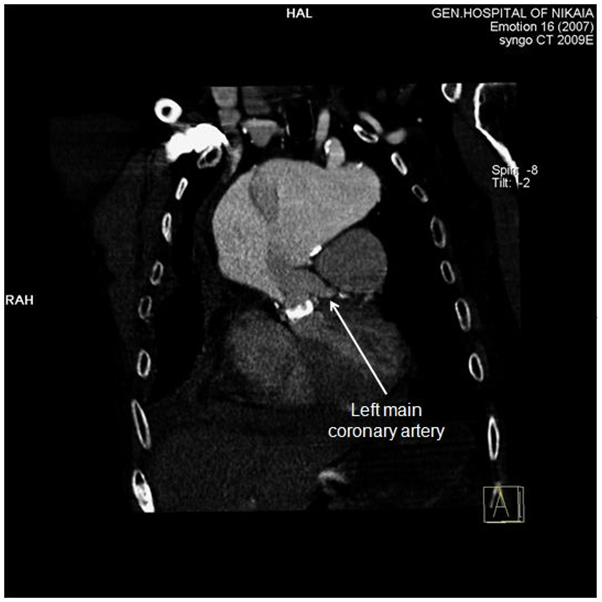

Due to patient’s history, a CT-angiography was immediately performed, which showed a massive perigraft aneurysm, 9x9.5 cm in maximum diameter, extended to the arch, compressing superior vena cava (SVC), brachiocephalic artery, right coronary artery (RCA), and graft partially detached from distal anastomosis, but within the aneurysmal sac Figure (2-7). The aneurysm was probably formed by a leakage at distal anastomosis, between the graft and the native aortic wall which was wrapped around it. A large right pleural effusion was also obvious. However, active leakage of the contrast agent from aneurysmal sac to the surrounding tissues was not observed at that point.

Figure 5 CT-angiography, anterior frontal view: Left main coronary artery is clearly demonstrated, while right coronary artery is compromised by the aneurysm.

Delay for intervention (surgical or endovascular) to this patient was proved fatal. However, surgical delay has been proposed over a decade ago for patients with type A dissection with malperfusion, dead or near-dead heart, limb, or visceral organ.10 Yet, there is a lot of controversy over this issue, and no solid guidelines exist, regarding malperfusion syndrome and acute type A aortic dissection.6 Advances in endovascular therapeutics will definitely change this field in the near future. Our patient actually had myocardial and brain malperfusion, demonstrated by electrocardiographic changes, rise of cardiac troponin I levels and cognitive impairment. Malperfusion of the heart derived from dynamic obstruction of RCA by the massive pseudoaneurysm (Figure 5), while malperfusion of the brain was caused by dynamic compression of brachiocephalic artery. Moreover, SVC syndrome was induced by pseudoaneurysm compression. As no active extravasation of the contrast agent from the aneurysmal sac to the surrounding tissues was visible at the time of CT-angiography, it is reasonable to imply that right pleural effusion at that time was transudate and produced by high central venous pressure at upper body.